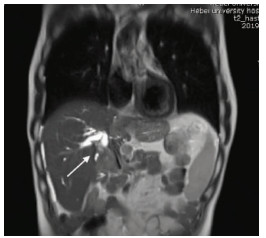

Multidisciplinary treatment of hepatocellular carcinoma with tumor thrombosis in the left portal vein: A case report

Jihong YANG, Guoxiang CHEN, Mo ZHOU, Jisen ZHAO, Yuan WANG, Yuanlong ZHOU

2021, 37(3): 666-679. DOI: 10.3969/j.issn.1001-5256.2021.03.031

Abstract(1233) HTML (573) PDF (3239KB)(76)

Abstract: